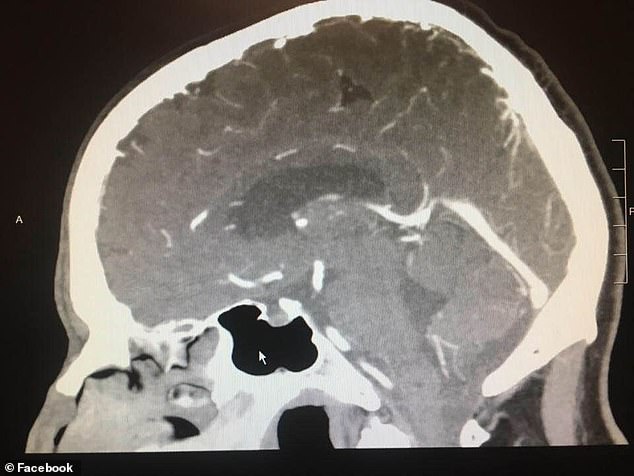

然而,就在做手术的前一天,伍德先生被告知手术取消了。其原因是:术前的X光片显示,他的脑部已无任何异常。

没有接受任何的治疗而迅速恢复健康,医学专家们也对此感到十分困惑。理查德·绮博士说,“我们有做测试,也有相关的医疗技术,我们试图得出一些结论。但是,有时我们仍无法解释某些现象。”